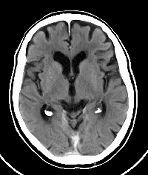

1. A study conducted by Tierney et al. in 2001 which utilizes PET scans to investigate the result of brain damage.

1. The aim was to evaluate, using PET scans, the bilingual language compensation following early childhood brain damage

1. The target population were 12 participants, who were fluent in sign language as well as MA.

1. The procedure: PET scanning technologies were used while the participants produced narrative speech or signs.

1. As a result MA's right hemisphere was more active than the others' during the production of both speech and sign language.

1. As a conclusion language function seems to have developed in the right hemisphere instead of the left hemisphere as an adaptation following his early brain damage

1. Biological Factor linked back to damage to brain, and specific areas. Behavior linked back to language, and language acquisition

2. Background: A 37 year old man (MA) with normal speech functions participate in a normal speech study, it was then discovered that he had a lesion in his left frontal lobe. A result of encephalitis he suffered at the age of 6 weeks. Both his parents were deaf and he used sign language at home. Researchers were curious to know if this might have had something to do with his ability to speak despite the brain damage, that should have prevented him from doing so.